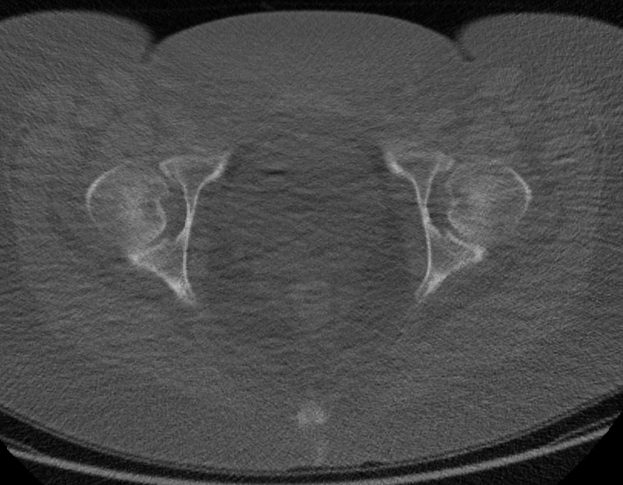

Prostatakrebs bleibt die häufigste Krebserkrankung bei Männern und die zweit tödlichste. Dennoch nehmen nur etwa 17 Prozent der Männer regelmäßig urologische Vorsorgeuntersuchungen wahr. Viele meiden die Termine aus Unbehagen gegenüber den Untersuchungen oder schlicht aus Zeitmangel.

Ärzte empfehlen mittlerweile den PSA-Bluttest als Hauptmethode zur Früherkennung von Prostatakrebs. Damit wird die ältere Methode der körperlichen Untersuchung ersetzt. Männern wird geraten, den ersten Test Mitte 40 durchzuführen, um einen Basiswert zu ermitteln und das persönliche Risiko einzuschätzen.

Ein PSA-Wert von 1,5 oder darunter bedeutet, dass die nächste Untersuchung erst in fünf Jahren nötig ist. Werte zwischen 1,5 und 3 erfordern alle zwei Jahre eine Kontrolle. Jeder Wert über 3 muss weiter abgeklärt werden. Auch ein starker Anstieg des PSA-Spiegels kann auf Krebs hindeuten.

Der Wechsel zur PSA-Testung soll die frühe Erkennung von Prostatakrebs verbessern. Männern wird empfohlen, ab Mitte 40 mit den Screenings zu beginnen, um ihr Risiko im Blick zu behalten. Ohne regelmäßige Kontrollen können Tumore in Prostata und Harnwegen unbemerkt bleiben, bis sie nur noch schwer behandelbar sind.